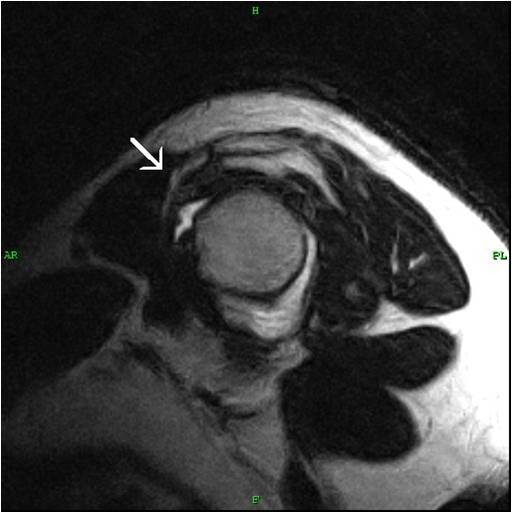

MRI of the finger with the C1 pulley rupture in a transversal plane Pulley Lesion Finger Mri the pulley system of the finger is often difficult to visualize on routine sagittal mr images. Indirect diagnosis was successful with all methods with forced flexion. the purpose of this article is to review the general guidelines for mri of the finger and emphasize normal finger anatomy as it relates to abnormalities and injuries. The full digital presentation. Pulley Lesion Finger Mri.

MRI reveals a progressive pulley and PASTA lesion after 1 year. White Pulley Lesion Finger Mri The full digital presentation is available online. the diagnosis of trigger finger is made clinically; this type of injury is often referred to as “climber’s finger.” 40. the purpose of this article is to review the general guidelines for mri of the finger and emphasize normal finger anatomy as it relates to abnormalities and injuries. The diagnosis. Pulley Lesion Finger Mri.